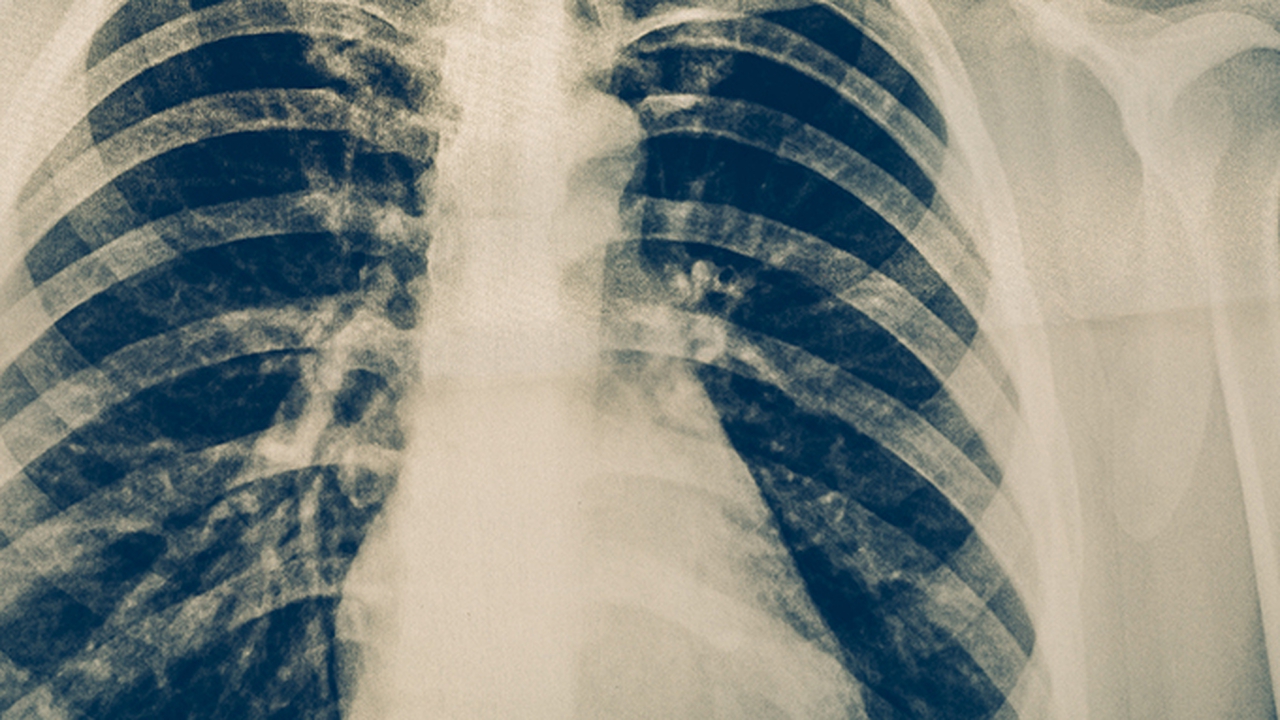

肺癌是一种常见的恶性肿瘤,发病原因复杂,与吸烟、空气污染、职业暴露等因素密切相关。早期发现和治疗对提高生存率至关重要。济南作为山东省的省会城市,拥有多家在肺癌治疗方面具有丰富经验的医院,为患者提供多样化的治疗选择。